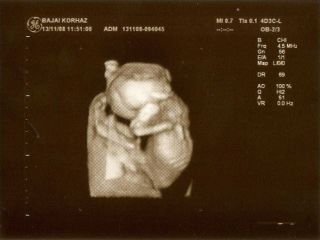

és hogy magamat is felviditsam ez után a rosszul sikeredett hét után, bejelentkeztem a babaexpon a 4D-re, itt csak 4ezer lesz, és hátha megmutatja magát a picurkánk!